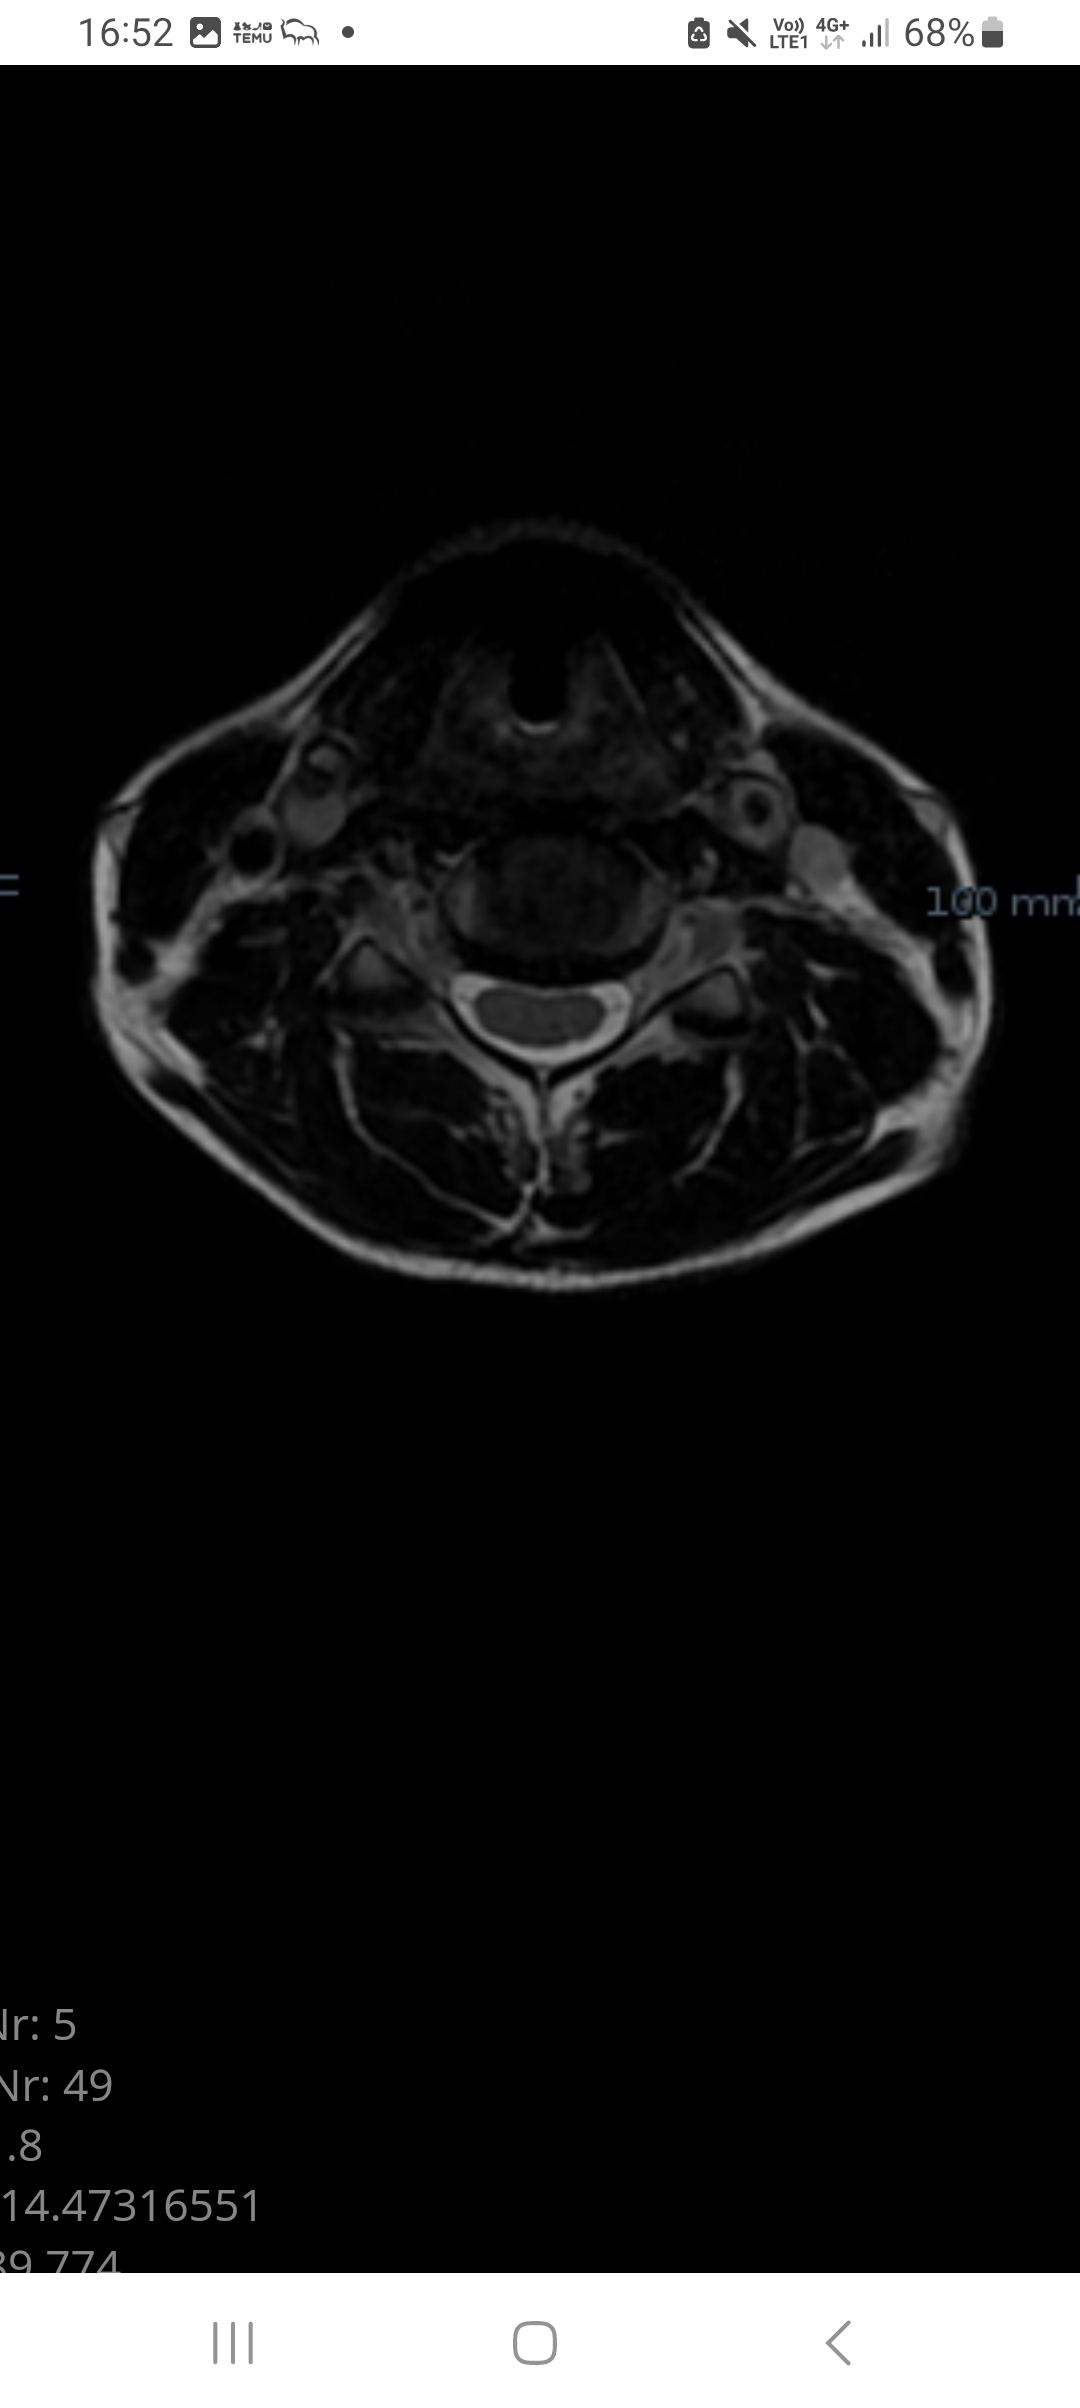

Mam 35 lat i przed sobą widmo kolejnej operacji, tym razem pięterko wyżej c5-c6. Znowu ogromna przepuklina (jeszcze sie nie oderwała) i uciska rdzeń. Tym razem objawy są mniej dokuczliwe, albo przez lata stałem się ignorantem. Ból potylicy, karku i ramion (dużo mniejszy niż przy poprzedniej przepuklinie), mrowienie i cierpnięcie rąk, mniejsza precyzja i mniejszy zakres ruchu głowa. Zgłosiłem się do lekarza który mnie operował ostatnio, a on stwierdził, że obraz rezonansu jest poważny ale moje objawy są mniej dokuczliwe i z racji tego, że to już drugi poziom miałby być operowany, to lepiej spróbować rehabilitacji, bo zaraz pójdzie kolejny dysk i kolejny i zostanę robotem. Szczerze, to jakoś umknęła mi informacja, że po zoperowaniu jednego odcinka - siadają kolejne. Myślałem, że zrobiłem to raz i mam to z głowy już na zawsze. Samej operacji się nie boję ale nie chce co 5 lat być operowany i stawać się terminatorem. Jest na to jakiś sposób? Czy uporczywa rehabilitacja może sprawić, że operacja nie będzie konieczna? Że to się nie będzie rozwijać? Boję się

Poniżej moje aktualne zdjęcie paszportowe